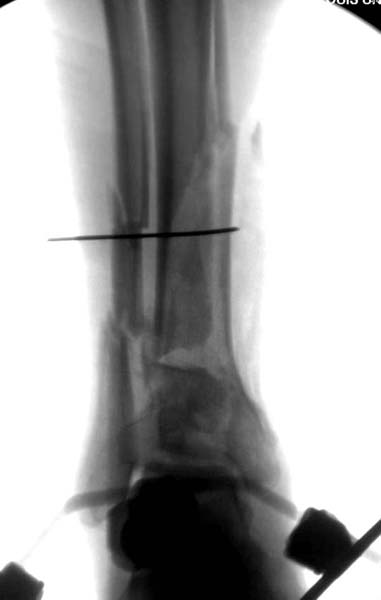

Через три дня повторная I&D, где через рану манипулировали дистальным фрагментом с установкой пары межфрагментарных шурупов. На рану вакуум и следующая обработка закончилась закрытием раны. Отек держался немного дольше, чем обычно.

После спадения отека вариантов фиксации много, включая мининвазивную технику, но данный случай закончили установкой простого аппарата Илизарова.